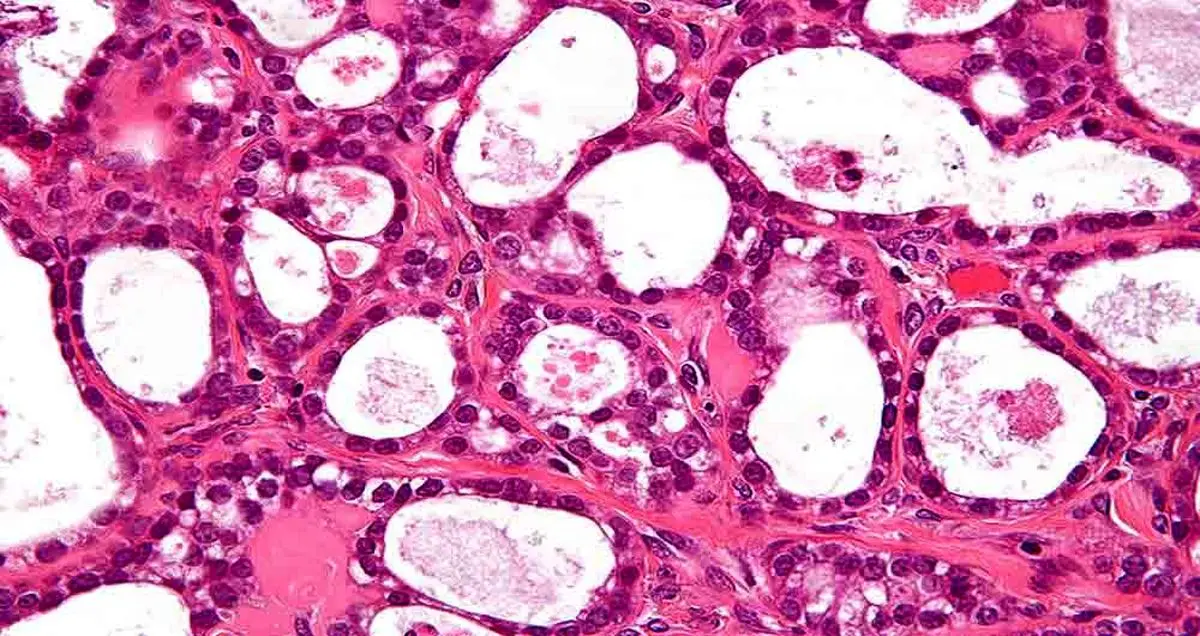

به گزارش کلیک، به تازگی محققان موفق شده‌اند با استفاده از سیلیکون متخلخل، شکل جدیدی theranostics را ایجاد کنند. این محققان با استفاده از سیلیکون متخلخل که جز‌ء نانوذرات سیلیکون محسوب می‌شود توانسته‌اند، به تشخیص سرطان و درمان آن بپردازند.

اسمینکینا به بیان این مطلب پرداخت که اعضای تیم تحقیقاتی او برای نخستین بار موفق شده‌اند از سیلیکون متخلخل در مرحله ترکیبی تشخیص و درمان بیماری‌ها یا همان theranostics، به عنوان ماده‌ای بی خطر در تشخیص و درمان بسیاری از انواع سرطان استفاده کنند. وی معتقد است که سیلیکون متخلخل نه تنها می‌تواند به راحتی به داخل سلول بیمار نفوذ کند، بلکه زمانی که سوراخ‌های این ماده با دارو پر می‌شود، می‌تواند آن‌ها را هنگام حل شدن در اسید سیلسیک رها سازد. به نظر اسمینکینا تیم تحقیقاتی او نتایج خوب و مهمی را به دست آورده‌اند که می‌توانند در تحقیقات بلند مدت جهت ایجاد سیلیکون متخلخل با قابلیت سازگاری زیستی و تجزیه پذیری برای انتقال دارو به سلول‌های بیمار، مورد استفاده قرار گیرند.